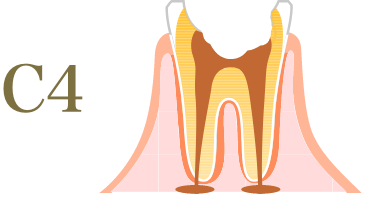

むし歯の進行度と治療方法

-

神経が死んでしまい、痛みを感じなくなる。

- 治療方法

- 抜歯後、

入れ歯やインプラントで補綴